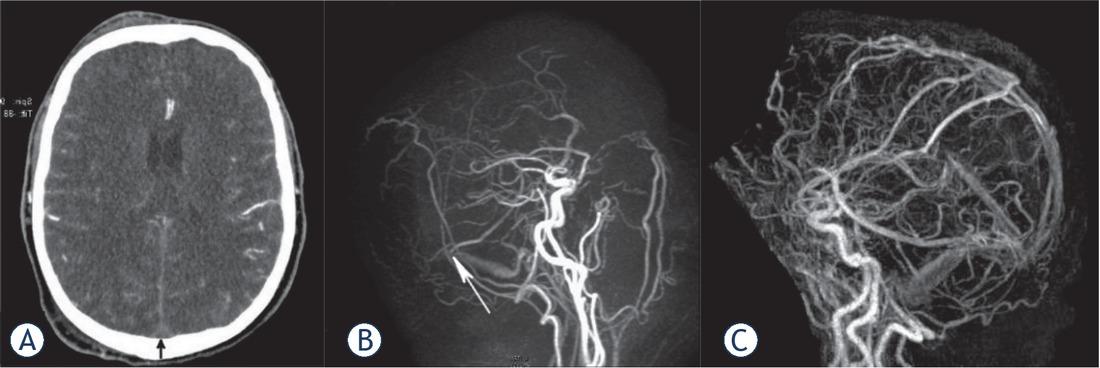

Figure 1